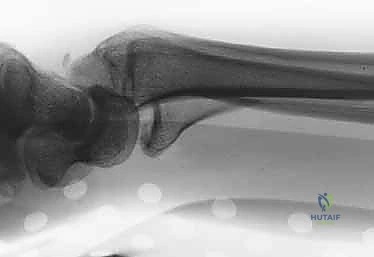

- الأشعة السينية (X-rays):

هي الخطوة الأولى لتقييم الكسر. يتم أخذ صور من زوايا متعددة (أمامية خلفية، جانبية، ومائلة) لتحديد موقع الكسر الأساسي ودرجة الانزياح والتقصير في عظم الكعبرة.

- تشوه مرئي (Deformity): في حالات الانزياح الكبير، قد يبدو الرسغ معوجاً أو منحنياً بشكل غير طبيعي. يُعرف التشوه الكلاسيكي باسم "تشوه شوكة العشاء" (Dinner Fork Deformity)، حيث ينزاح الرسغ للخلف.